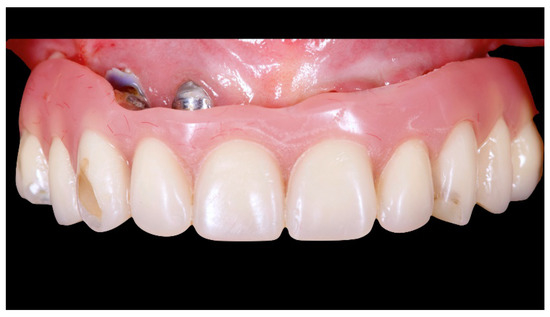

Figure 13.

Final prosthesis mounted. Note the through holes. In two cases, it was compensated with only the Seeger, without a through screw.